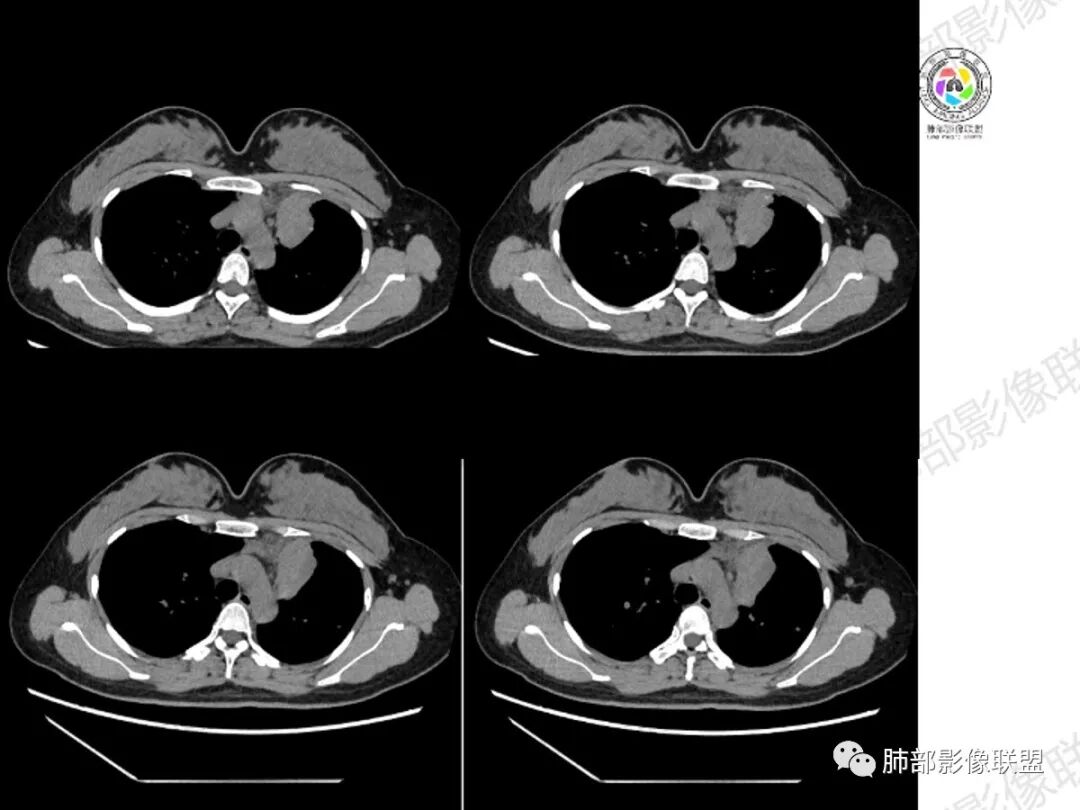

年轻女性,咳嗽咳痰一个月,左肺体积缩小,左肺尖部胸膜下实变影,宽基底与胸膜相贴,病灶边缘平直收缩,部分略膨隆,病灶下方可见支气管挤压,肺窗所示:周围伴有多发结节部分可见树丫征,纵隔窗可见病灶与纵隔胸膜黏连,部分与左肺动脉分界欠清,平扫密度尚均匀,增强扫描不均匀强化,内部可见多个低密度坏死,伴有条状血管影,纵隔淋巴结略有肿大。

胸部CT:左肺体积缩小,左肺上叶前段纵隔旁胸膜下大片实变影,边缘清楚、匀齐、平直收缩,部分略膨隆,周围多发结节、树芽卫星灶,纵隔窗病灶与纵隔胸膜黏连,实变内多发点状钙化。平扫密度尚均匀,增强扫描不均匀明显强化,多个低密度区,呈仙人掌样,伴有条状血管影,考虑慢性炎症伴左上叶前段支气管闭塞,TB?鉴别黏表、腺癌等。